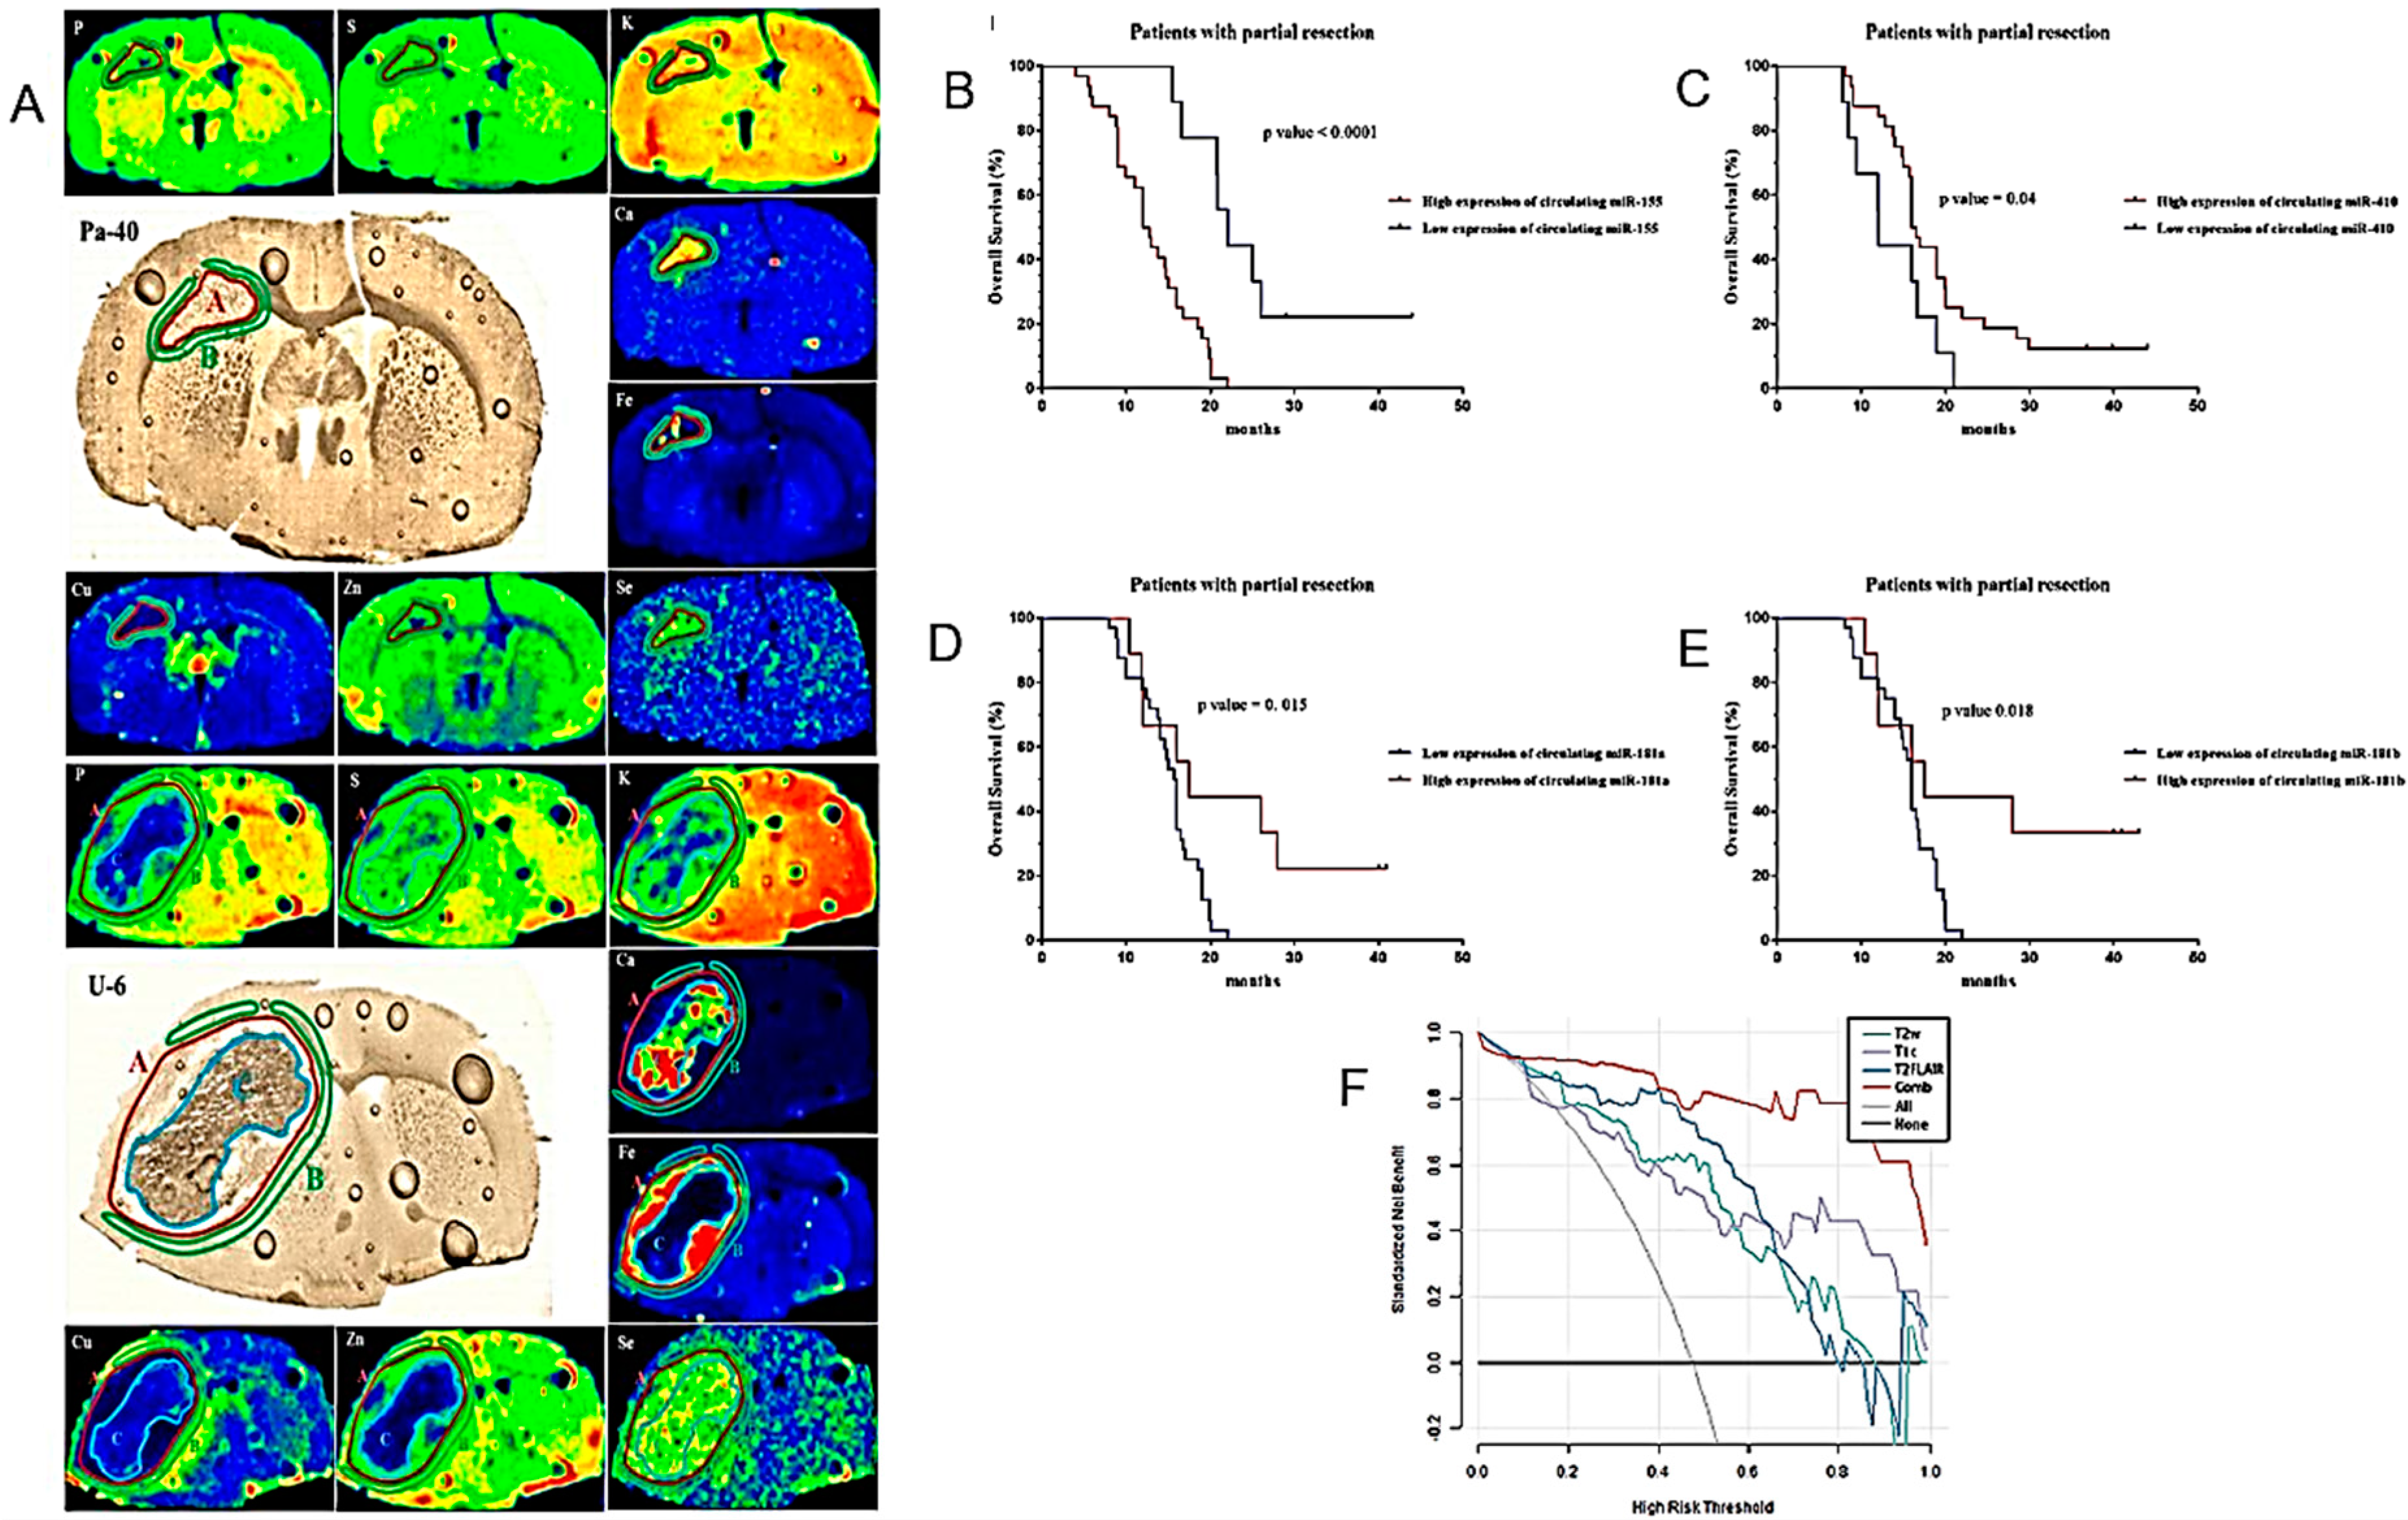

| Increased accumulation of Fe and Se in tumor and Cu in peritumoral tissue in rodent models. | Orthotopic rat models of GB. | [103] |

| Circulating miR-181a/b, miR-410 and miR-155 as diagnostic and prognostic biomarkers in HGG. | Determination of pre- and postoperative plasma levels of miR-181a/b, miR-410 and miR-155 in 114 HGG patients, 77 LGG patients and 85 healthy volunteers as control group. | [105] |

- Planeta, K.; Setkowicz, Z.; Czyzycki, M.; Janik-Olchawa, N.; Ryszawy, D.; Janeczko, K.; Simon, R.; Baumbach, T.; Chwiej, J. Altered Elemental Distribution in Male Rat Brain Tissue as a Predictor of Glioblastoma Multiforme Growth-Studies using SR-XRF Microscopy. Int. J. Mol. Sci. 2022, 23, 703. [Google Scholar] [CrossRef] [PubMed]

- Wu, J.; Al-Zahrani, A.; Beylerli, O.; Sufianov, R.; Talybov, R.; Meshcheryakova, S.; Sufianova, G.; Gareev, I.; Sufianov, A. Circulating miRNAs as Diagnostic and Prognostic Biomarkers in High-Grade Gliomas. Front. Oncol. 2022, 12, 898537. [Google Scholar] [CrossRef] [PubMed]